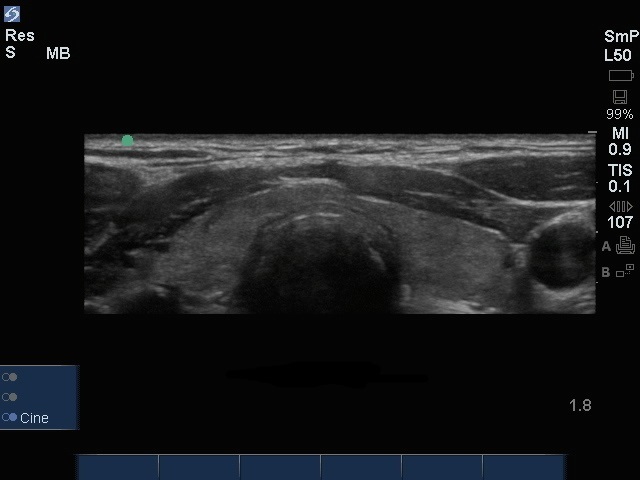

甲状腺横Edge画像